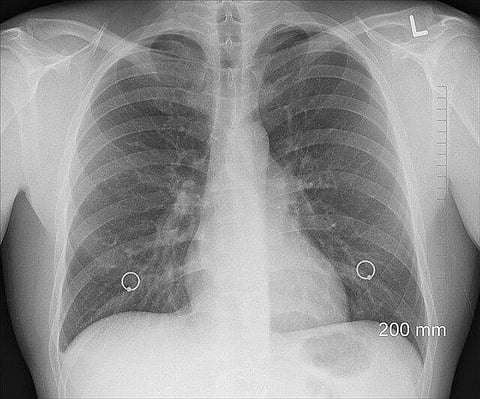

When we inhale isolated coronavirus particles, more than 65 percent reach the deepest region of our lungs. Pixabay

The study also revealed that more virus particles are deposited in the right lung, especially the right upper lobe and the right lower lobe, than in the left lung. This is due to the highly asymmetrical anatomical structure of the lungs and the way air flows through the different lobes.

The research is backed up by a recent study of chest CT scans of Covid-19 patients showing greater infection and disease in the regions predicted by the model.